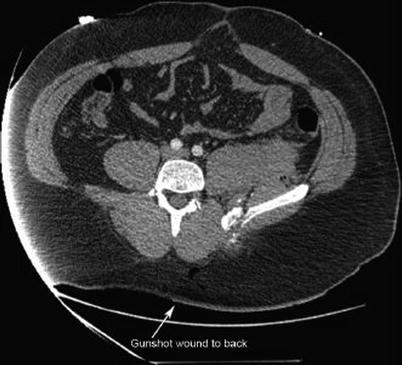

Fig. 16.2

Gunshot wound to back with evidence of intraperitoneal penetration. Patient found to have multiple enterotomies at laparotomy